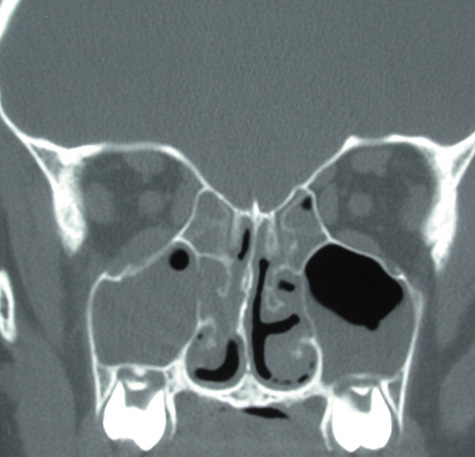

Alternatively, the disease can present in the healthy host in a noninvasive form as sinus mycetoma or allergic fungal sinusitis.106 A colony of organisms forms a mycetoma in a sinus and gives rise to a chronic sinusitis. This type of aspergillosis is more common in hot humid climates. These patients present with nasal congestion, postnasal drip, and chronic sinus pain, along with frequent bouts of acute sinusitis. A mass is seen that originates from an adjacent sinus that may have sclerotic margins and can produce an adjacent inflammatory reaction within the orbit. This form responds well to surgical debridement with restoration of normal sinus drainage and does not require intravenous anjpgungal therapy.114 Allergic fungal sinusitis is an allergic reaction to aerosolized environmental fungi and causes patients to suffer from headaches and nasal stuffiness. Patients may also present with proptosis and extraocular muscle entrapment. Treatment consists of surgical debridement and steroids without anjpgungals.106,109,112

Computed tomographic findings in patients with both forms of the disease demonstrate areas that are almost metallic in density. These foci of irregularly calcified bone on CT may be pathognomonic (Fig. 22). On MRI, these areas appeared bright on T1-weighted imaging and have decreased signal on T2-weighted images, which may be related to the presence of ferromagnetic materials such as iron and manganese within the fungal concretions.115

Fig. 22. Aspergillosis. Computed tomography shows areas of extreme density of the ethmoidal bones.